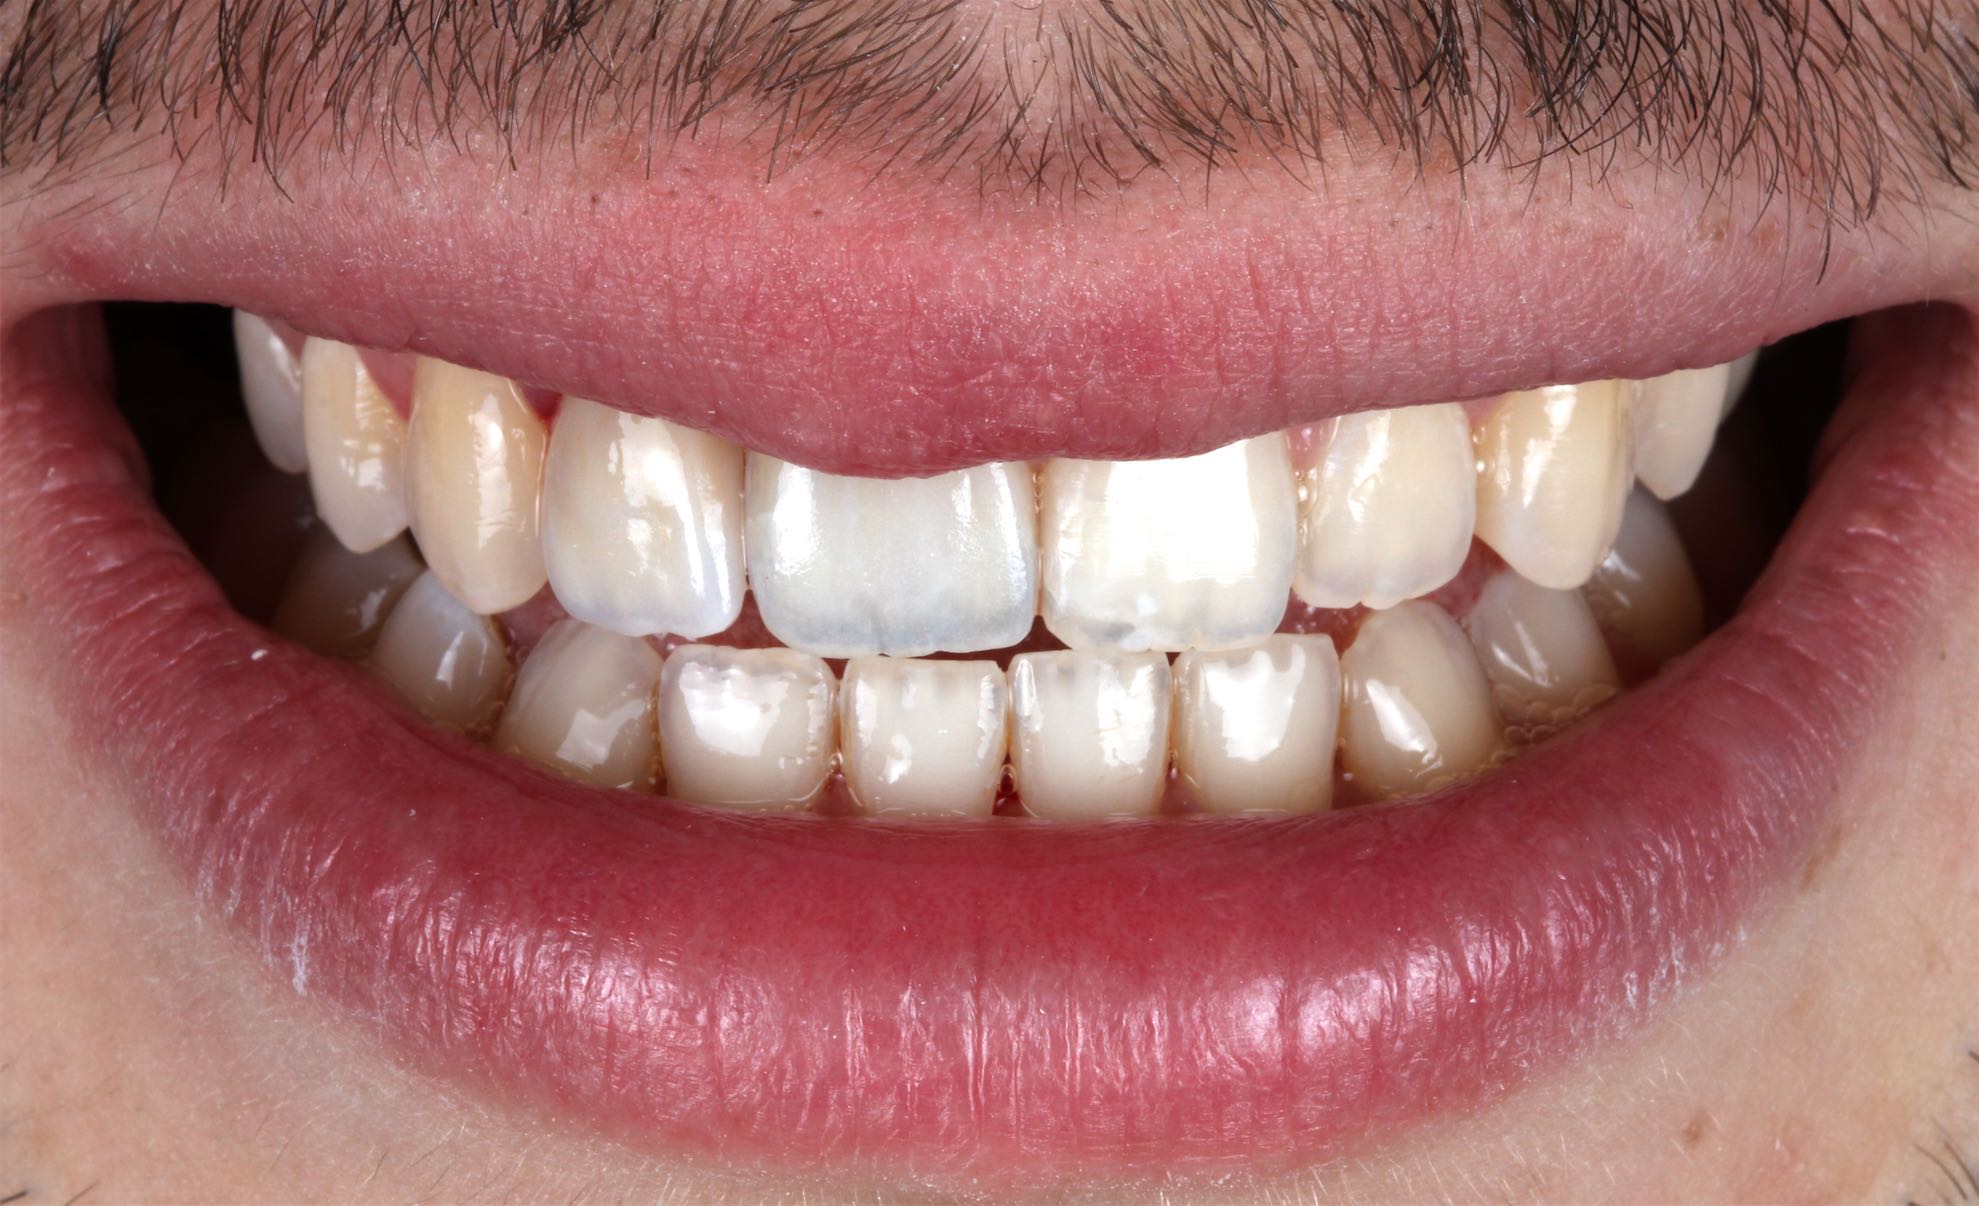

Odontología Estética. Coronas

BeforeAfter